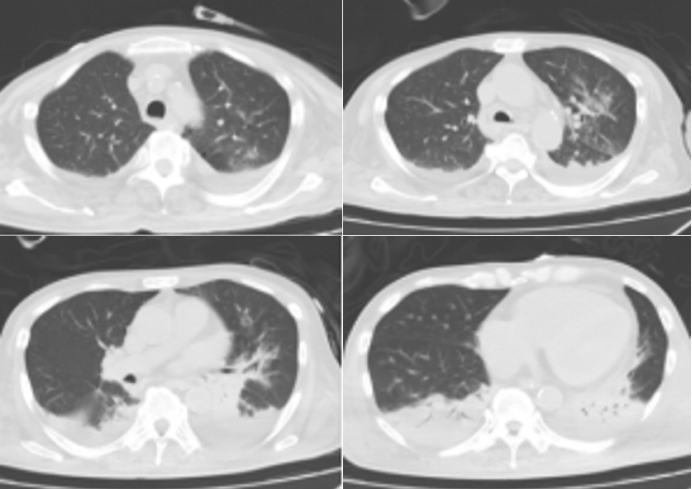

入院胸部CT:双肺渗出性病变,双侧胸腔积液伴双肺下叶膨胀不全,主动脉及冠状动脉钙化,心包少许积液,心腔密度减低;肝硬化不除外,脾大,腹腔积液(如图1)。

图片

1  患者入院胸部CT